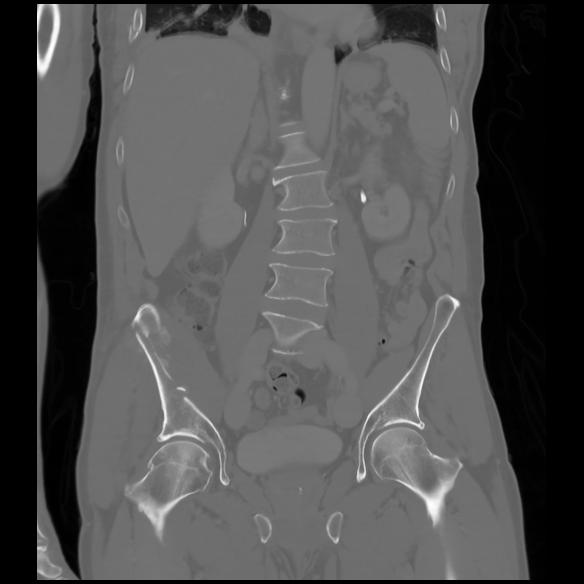

6 CUERPO,CE,Coronal,3.000,CUERPO,Coronal,